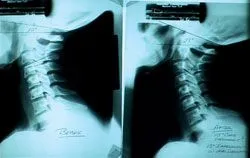

These following pictures are X-rays taken from one of Dr. Klinger's patients after an automobile accident.

If you look at the first X-ray there has been a loss of the normal neck curve due to the forces of a 10 mph automobile accident.

With proper and specific chiropractic care at my office the curve is re-established avoiding significant degenerataive changes and perment symptoms.